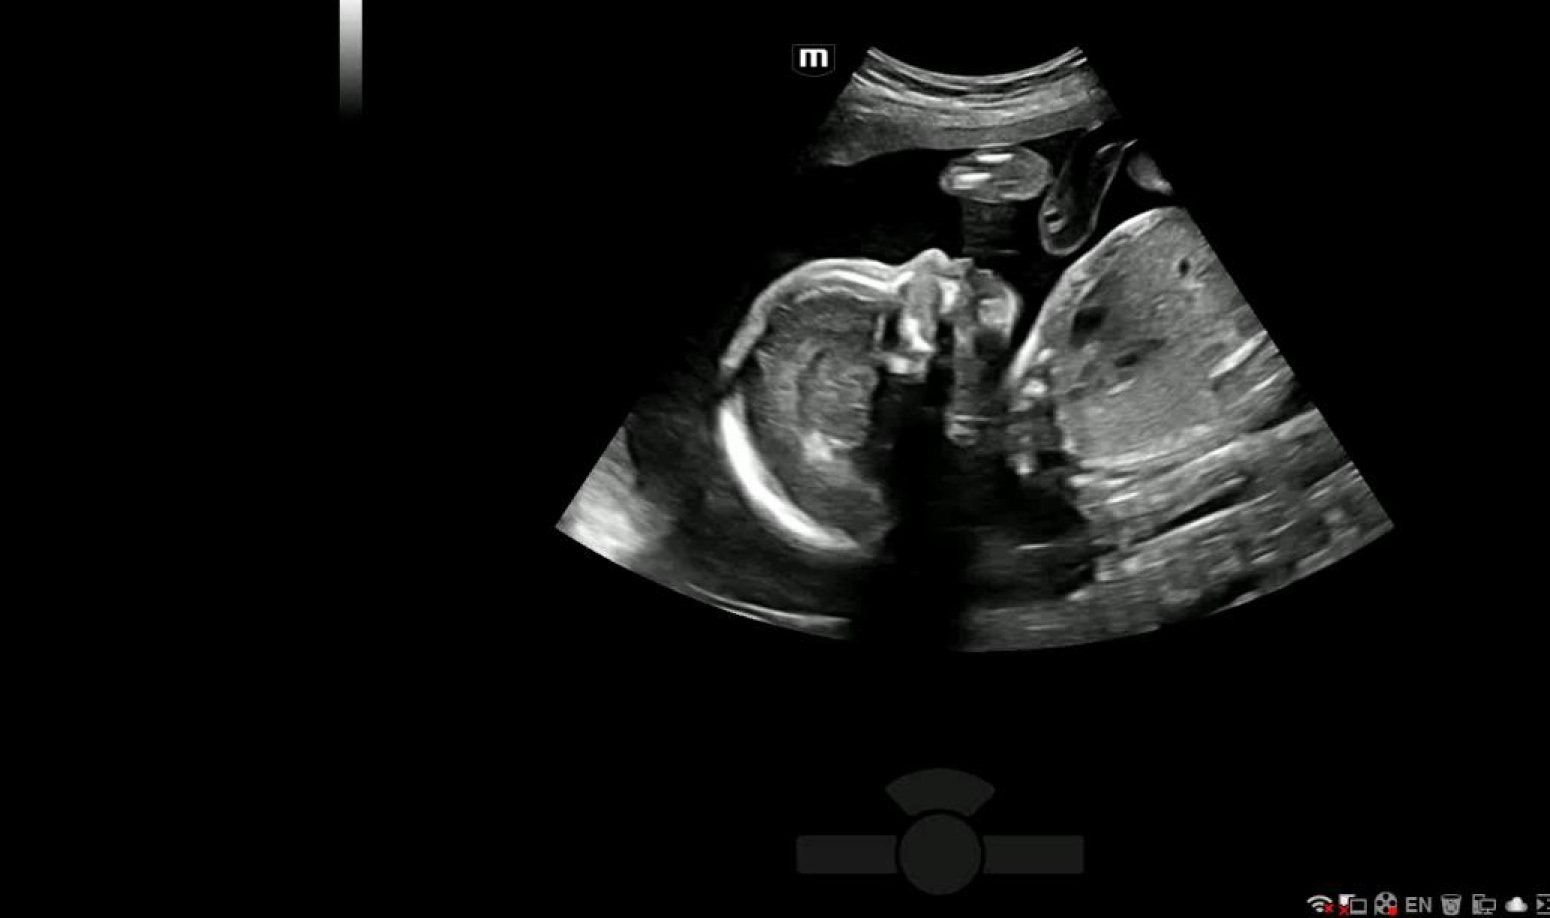

С легкостью получайте потрясающие объемные изображения лица плода.

- Автоматическое распознавание лица плода

- Автоматическая подстройка зоны интереса и положения до оптимального

- Автоматический определение параметров рендеринга лица плода